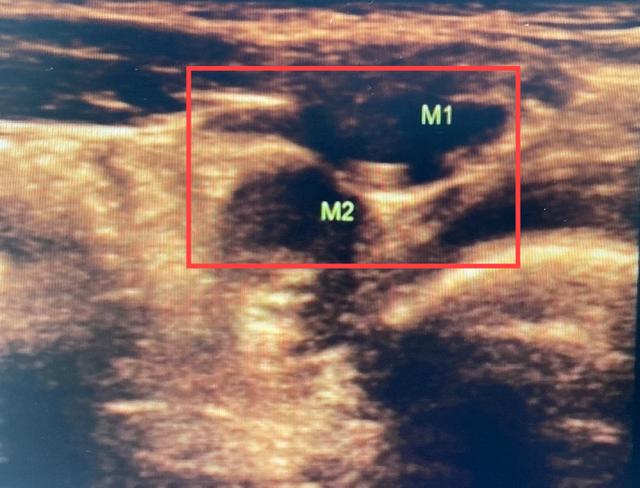

在给小飞进行腹部超声检查后,徐晓龙副主任医师发现小飞右侧的“蛋蛋”极有可能异位到左侧腹股沟内环口处。

入院后,进一步进行盆腔MR扫描,小飞左侧腹股沟区存在两个异常信号影,徐晓龙副主任医师判断小飞左侧隐睾、右侧睾丸异位的可能性极大。

MR显示左侧腹股沟区有两个异常信号影